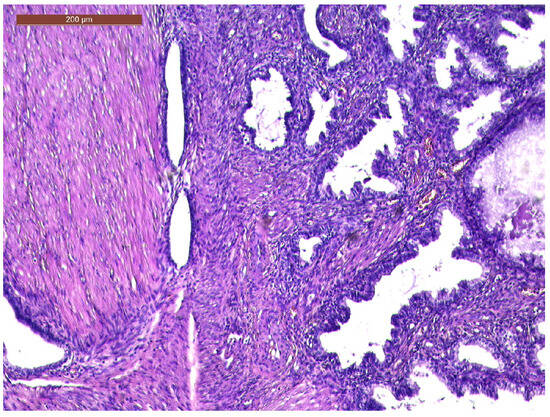

The histopathological exam revealed the tissue fragments to be sufficiently delimited by a thin layer of the endometrium composed of a biphasic stromal and glandular proliferation and represented by cellular stroma with edematous areas with thin blood vessels interspersed with thick bundles of smooth muscular fibers that included irregularly contoured secretory endometrial glands (Figure 4 and Figure 5), organized in hyperplastic lobular areas, and lined by the simple and pseudostratified epithelium with hyperchromatic nuclei (Figure 6), eosinophilic metaplasia, and a tendency for squamous differentiation.

Our microscopic findings are consistent with the following histopathological characteristics that define the atypical polypoid adenomyoma: a well-circumscribed biphasic tumor composed of endometrioid glands with a complex or lobular histoarchitecture, squamous morular metaplasia, and sometimes cytologic atypia, interspersed with a fibromyomatous stroma, which may present myxoid change.

Figure 4. Endometrial glands with lymphoid follicles and associated smooth muscle fibers (HE × 10).

Figure 5. Thick bundles of smooth muscle fibers interspersed with endometrial areas containing irregularly oriented glands and dense cellular stroma (HE × 10).